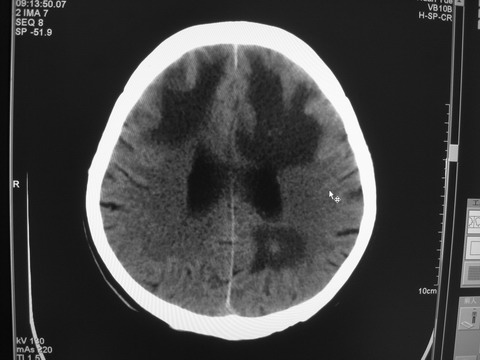

患者 男 69岁 头晕头痛不适

多发病灶,指状水肿,首先诊断转移瘤。

多个结节并周围大面积水肿区,多考虑多发性脑转移瘤

小病灶、大水肿,病灶多发,首先考虑多发转移瘤;建议查原发灶。

额顶叶多发小病灶、大水肿,首先考虑多发转移瘤;建议查原发灶

脑内多发病灶,小病灶,大水肿。

典型转移性肿瘤。

应进一步检查,查找原发病灶。

结果 : 该患者结肠癌病史5年 考虑脑转移